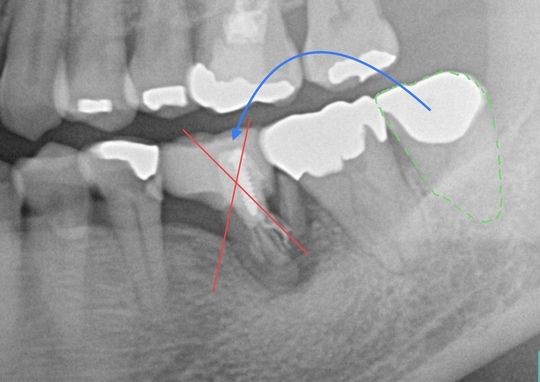

歯の移植治療症例1 治療前

左下の奥歯が根が割れて保存不可能です。奥の咬合わせの余っている親知らずを移すことににしました。移植した歯は、根管治療とクラウン修復が必要です。

初診時

奥3番目の歯の根が割れています。